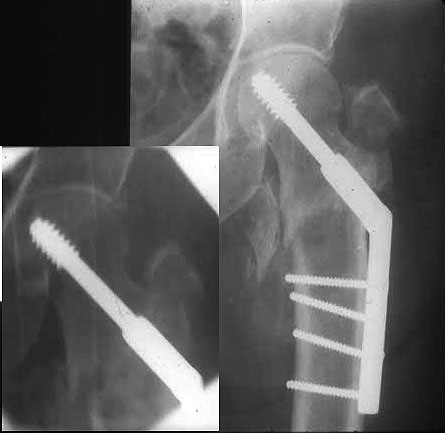

Это 4-фрагментный перелом, традиционно-современная фиксация - это динамический бедренный винт, DHS. Либо какой-либо из проксимальных бедренных гвоздей, предназначенных для ранней полной нагрузки, из-за меньшего доступа, других преимуществ перед DHS нет. Если доступен только реконструкционный гвоздь, то винты вводить надо очень точно и аккуратно субхондрально, т.е. максимальной длины, а то прорежутся в головке.

Вот пример наших американских коллег про DHS. Видно, как стелескопировались отломки, хотя поначалу был оставлен диастаз.